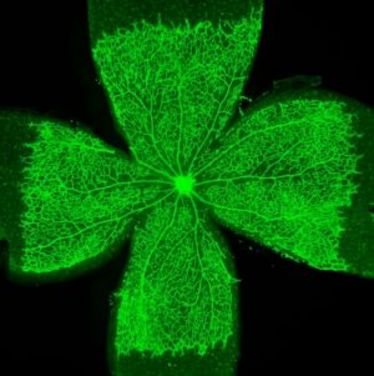

Ein fein verästeltes Netzwerk aus Blutgefäßen versorgt alle Organe des Menschen mit Nährstoffen und entfernt schädliche Stoffwechselprodukte aus den Geweben. Das Wachstum dieses Gefäßsystems ist für alle Entwicklungs- und Heilungsprozesse von größter Bedeutung. Umgekehrt kann unkontrolliertes Blutgefäßwachstum auch Krankheitsprozesse fördern – so wie beispielsweise Hämangiomen, schwammartigen Gefäßwucherungen in der Haut, oder Retinopathien im Auge von Diabetikern und alternden Menschen.

Ein fein verästeltes Netzwerk aus Blutgefäßen versorgt alle Organe des Menschen mit Nährstoffen und entfernt schädliche Stoffwechselprodukte aus den Geweben. Das Wachstum dieses Gefäßsystems ist für alle Entwicklungs- und Heilungsprozesse von größter Bedeutung. Umgekehrt kann unkontrolliertes Blutgefäßwachstum auch Krankheitsprozesse fördern – so wie beispielsweise Hämangiomen, schwammartigen Gefäßwucherungen in der Haut, oder Retinopathien im Auge von Diabetikern und alternden Menschen.